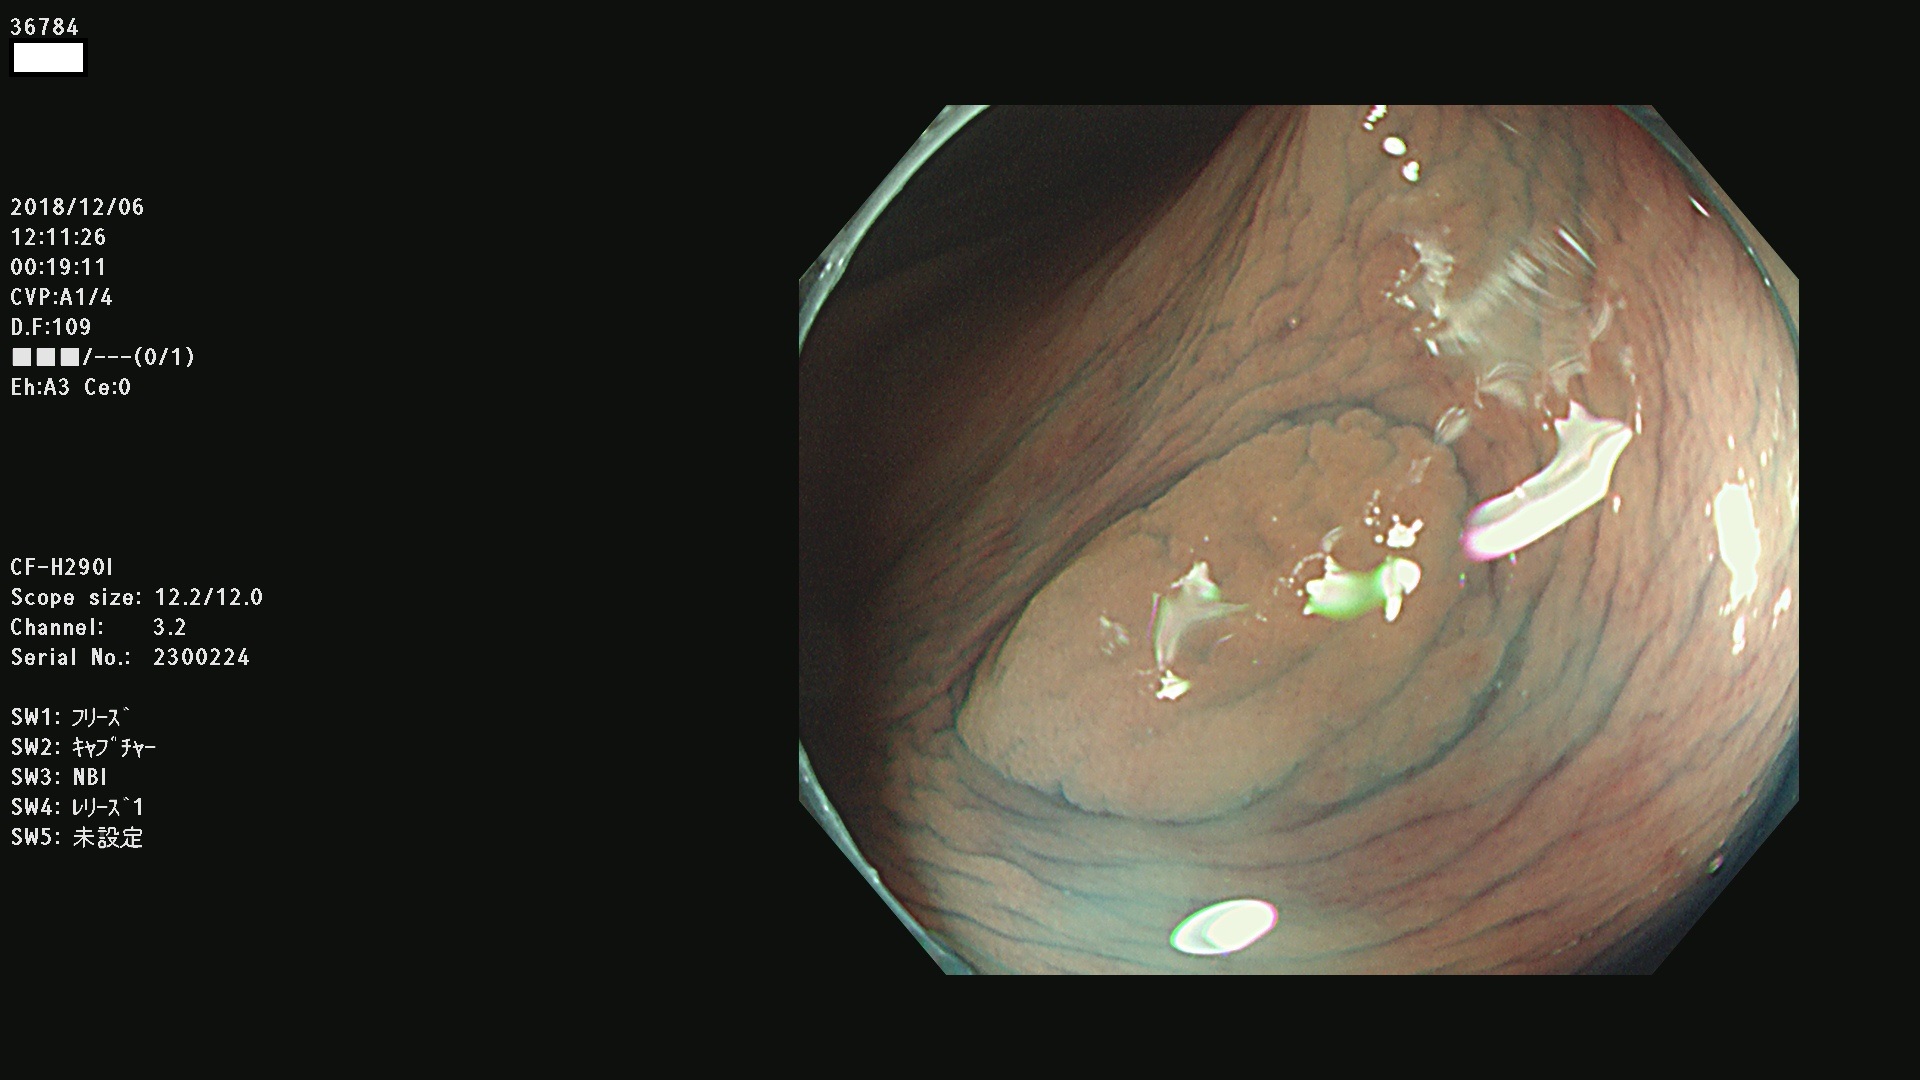

発見困難で危険性の高い平坦型病変(上記100名より抽出)